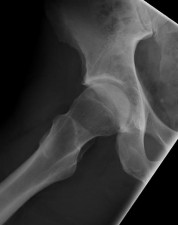

(SAE09TR.72) A 13-year-old girl sustained an isolated midshaft left femoral fracture in a motor vehicle accid…